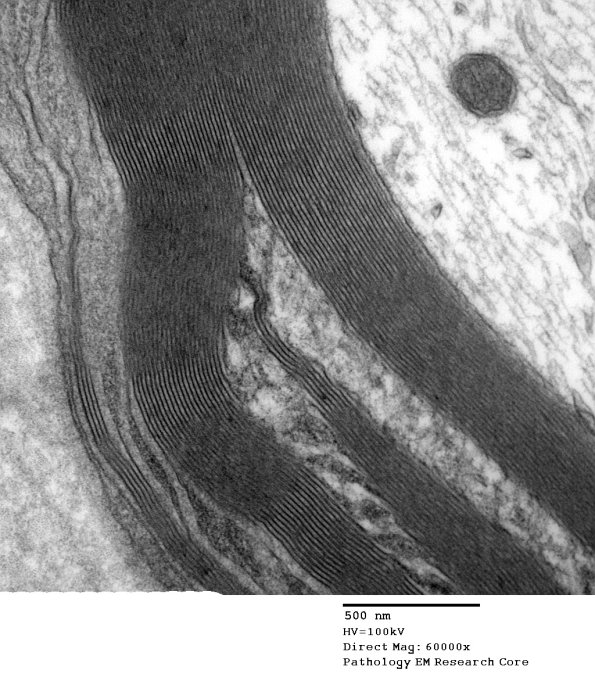

4A2-5 Higher magnification images of the SLC. (Electron micrographs)